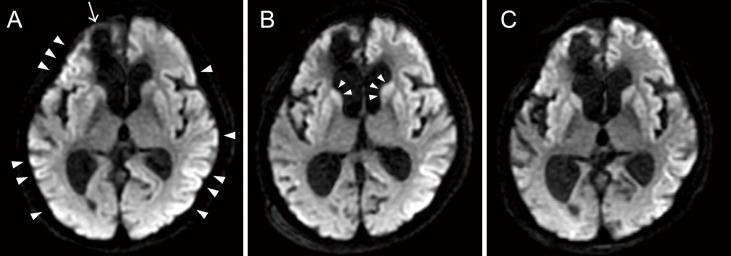

In this study, we report on a case of probable sporadic Creutzfeldt-Jakob disease (sCJD) diagnosed after a difficult course of status epilepticus (SE) in a patient with poststroke epilepsy. The patient was admitted with progressive cognitive decline and convulsive SE; therefore, it was initially thought that the patient had developed SE due to nonadherence to antiseizure medication (ASM) use, but despite treatment with ASMs after admission, no improvement was noted in consciousness disturbance or lateralized periodic discharges (LPDs) on electroencephalogram (EEG) examination. After a refractory course, the progression of LPDs to generalized periodic discharges (GPDs) on EEG and abnormal magnetic resonance imaging (MRI) findings met the diagnostic criteria of sCJD. Even if the patient had epilepsy, such as poststroke epilepsy, as in this case, it is essential to consider other underlying causes, including CJD in cases of superrefractory SE.

在本研究中,我们报告了一例可能为散发性克雅氏病(sCJD)的病例,该病例是在一名患有中风后癫痫的患者经历了艰难的癫痫持续状态(SE)病程后被诊断出来的。患者因进行性认知衰退和惊厥性SE入院;因此,最初认为患者是由于未坚持使用抗癫痫药物(ASM)而发生SE,但尽管入院后使用了ASM治疗,意识障碍或脑电图(EEG)检查中的侧化周期性放电(LPD)均未改善。经过一个难治性病程后,EEG上LPD进展为全身性周期性放电(GPD)以及异常的磁共振成像(MRI)结果符合sCJD的诊断标准。即使患者患有癫痫,如本例中的中风后癫痫,在超难治性SE的情况下,考虑包括CJD在内的其他潜在病因也是至关重要的。